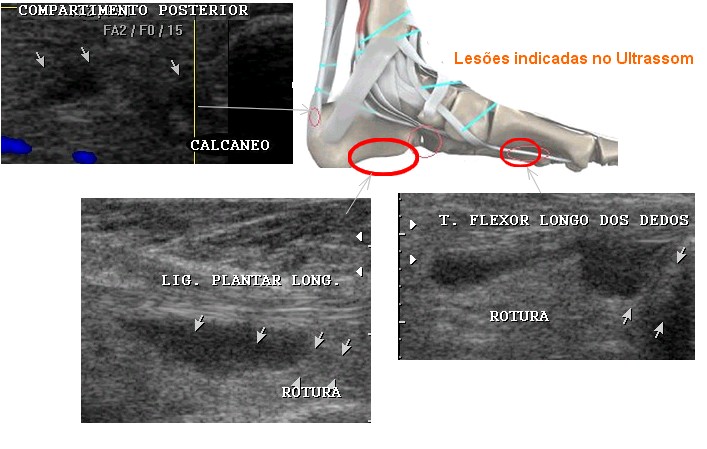

Coloco a evolução do trauma no pé direito

que sofri em 20 de março de 2008.

Coloco a evolução do trauma no pé direito

que sofri em 20 de março de 2008.

Com melhora em uma semana comecei a apoiar o calcanhar no chão,

o que resultou em recrudescência dos hematomas, edemas, e dores nestas

regiões que irradiavam para os músculos da perna.